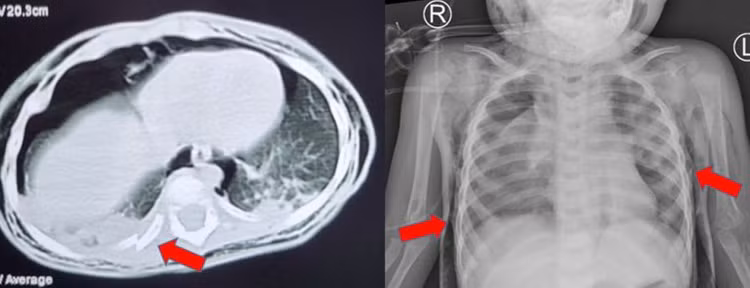

Tại đây ghi nhận trẻ đừ, môi tím, khó thở, SpO2 85% được đặt nội khí quản, thở máy, chụp CT scan đầu ngực bụng ghi nhận tràn khí dưới da vùng bụng, hông, lưng, ngực, cổ 2 bên, xẹp thùy trên phổi 2 bên và thùy giữa phổi (P).

Mất liên tục thành khí quản cạnh gốc carina bên (P), theo dõi vỡ khí quản, tràn khí trung thất – gãy xương sườn 8, 9, 10. Không thấy khối choán chỗ trong hộp sọ.

| CT scan và Xquang phổi cho thấy trẻ bị tràn khí trung thất, tràn khí dưới da, gãy xương sườn - Ảnh BVCC |